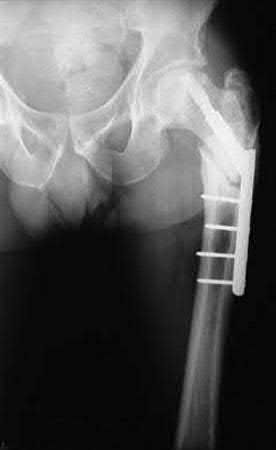

A 35-year-old-male sustains the fracture seen in Figure A. Which of the following reduction forces must be applied to the proximal fragment to correct the deformity commonly seen in these fractures?

Figure A demonstrates a displaced subtrochanteric femur fracture with an intact lesser trochanter. The pull of iliopsoas on the lesser trochanter as well as the intact external rotators and gluteal musculature results in the the proximal fragment being in a flexed and externally rotated or abducted position (the most common post operative deformity). Reduction manuevers must be biologically friendly but also counteract the flexion/abduction moment. Lundy's review article discusses evaluation and treatment of subtrochanteric fractures. The review article details the various implants often used which include 95 degrees plates, femoral reconstruction nails, or trochanteric femoral nails with interlocking options. Lundy's article discourages the use of the 135 degree screw and side plate combo due to high failure rates in these fracture patterns. Bedi et al also review treatment of these fractures and discuss common

problems of malunion, nonunion, and implant failure. The article reviews reduction techniques that are soft tissue friendly, as well as the use of appropriate implants in these fracture types.